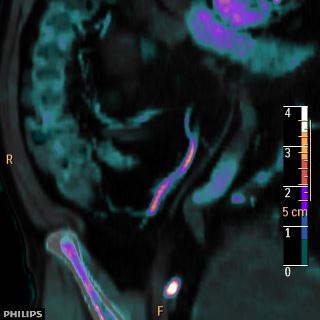

Coronal oblique with iodine overlay: Note the ureteral dilatation above and below the enhancing mass.

And the Goblet sign!